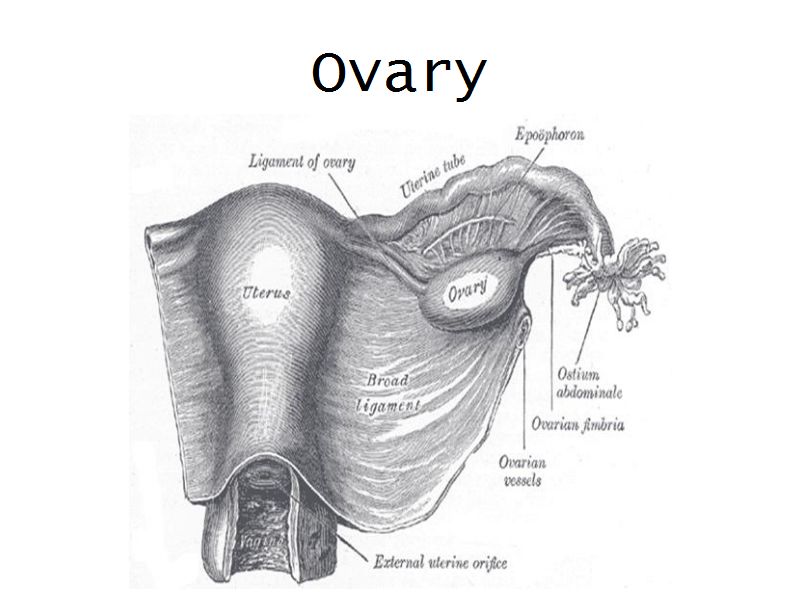

Ovary

- Capsule covered by modification of peritoneum

- Called germinal epithelium

- Simple squamous/cuboidal

- Subdivided

- Not clearly defined

- Cortex - contains ovarian follicles

- Medulla - vascular

Medulla

- Blood vessels

- Hilus cells

- Stroma

Blood vessels

- Enter medulla at hilus

- Supply the cortex

- Epithelioid cells clump around blood vessels

Epithelioid cells

- Located in hilus

- Also called hilus cells

- Clump around blood vessels

- ≈ Leydig cells

- Probably produces androgens